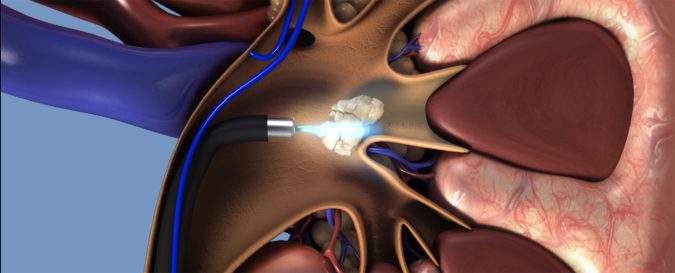

Istri saya punya masalah: posisi batu di ginjalnya sulit diambil. Harus dengan alat istimewa. Adanya di Amerika, Jerman, Jepang atau Samarinda.

Batu itu bisa saja diambil dengan cara dibedah. Tapi, kalau bisa, dihindari. Apalagi istri saya punya kebun tebu, eh, pabrik gula: di pangkreasnya.

Alat yang mirip itu ada juga di Surabya. Atau Jakarta. Tapi typenya bukan yang fleksibel. Yang bisa belok. Yang bisa mengarah ke lokasi batu. Yang nylempit sekali pun.

Di Samarinda? ”Benar. Samarinda. Satu-satunya di Indonesia,” ujar seorang ahli urologi di Surabaya.

Nama alat itu: flexible ureteroscooe (fURS). Di rumah sakit lain sydah banyak yang punya. Ureteroscope juga. Tapi bukan yang type flexible. Yang bisa belok-belok.

Dengan alat itu dokter Boyke bisa melakukan: retrograde intrarenal surgery. Atau RIRS. Untuk mengambil batu ginjal yang nylempit sekali pun.

Di Mount Elizabeth Singapura ada juga alat yang seperti di Samarinda. Tapi generasinya yang lama. Yang kekuatan lasernya hanya 60 watt. Sedang yang di Samarinda: 100 watt.